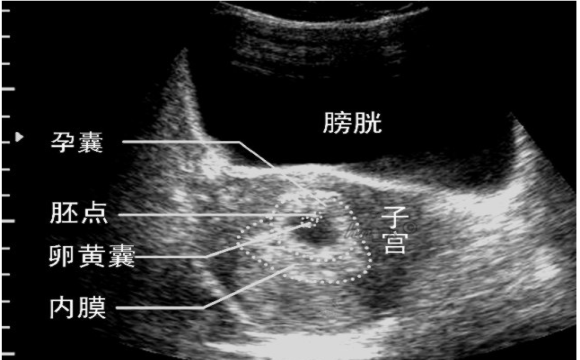

医院通过对女性的怀孕时间、孕囊大小、孕囊着床位置、年龄、体能情况,进行医生定制、技术定制、护理定制、康复定制等医疗服务,让患者在安全、舒适的就医环境中,轻松、便捷解决爱的意外。

◎孕囊大小:孕囊的大小决定着人流手段的选择。一般5MM<孕囊<50MM时,进入了胚胎期,此时羊膜腔扩大,原始心血管出现,可有搏动,是做人流手术的合适时期。

◎孕囊着床位置:孕囊位置在子宫的宫底、前壁、后壁、上部、中部都属正常,在其他情况都符合的情况下,可以进行人流。若孕囊为不规则形、模糊,且位置在下部,人流方式一定要谨慎选择。孕卵在子宫腔外着床发育,此时女性们要慎重,这是常见的宫外孕症状,很容易造成阴道出血,以至休克,此时不宜进行人流手术。

◎子宫壁厚度:一般来说子宫内膜正常的厚度是8-10MM,若是女性的子宫壁厚度薄弱,不仅会造成女性习惯性流产,也会导致受精卵无法附着在子宫壁上,出现不孕的情况。在进行人流时,甚至会造成子宫穿孔,危及女性生命安全。